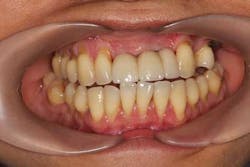

A 43-year-old female with a noncontributory medical history taking no medication and having no known food/drug allergies presented to my general dental office with a chief complaint of having “loose teeth with an underbite.” Clinically, she had generalized, moderate, chronic periodontal disease and was missing teeth Nos. 8 through 10. She had a Class III malocclusion with pathologic flaring of her remaining anterior teeth. She had both vertical and horizontal tissue loss in the No. 8 through 10 region. The patient wore a transitional partial denture to replace the anterior missing teeth that was placed in edge-to-edge occlusion by her previous dentist. (Fig. 1) She did not like having a removable prosthetic and desired a fixed option in the form of implants to replace her missing teeth. I sent her to the periodontist for a periodontal consult for her remaining dentition and dental implants to replace her missing front teeth.